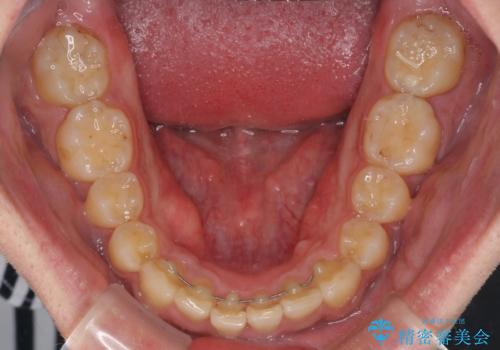

- 上下前歯のデコボコと下の前歯が隠れるほどの深い咬み合わせを気にして来院された患者様です。

インビザラインによる上下歯列の拡大と、IPR(歯と歯の間を削る)にるスペースの獲得により、口元のデコボコとディープバイトを改善することとしました。

デコボコがなくなったことで日頃の清掃が行いやすくなり、深い咬み合わせが改善したことで、食いしばりによる顎の負担も軽減されました。